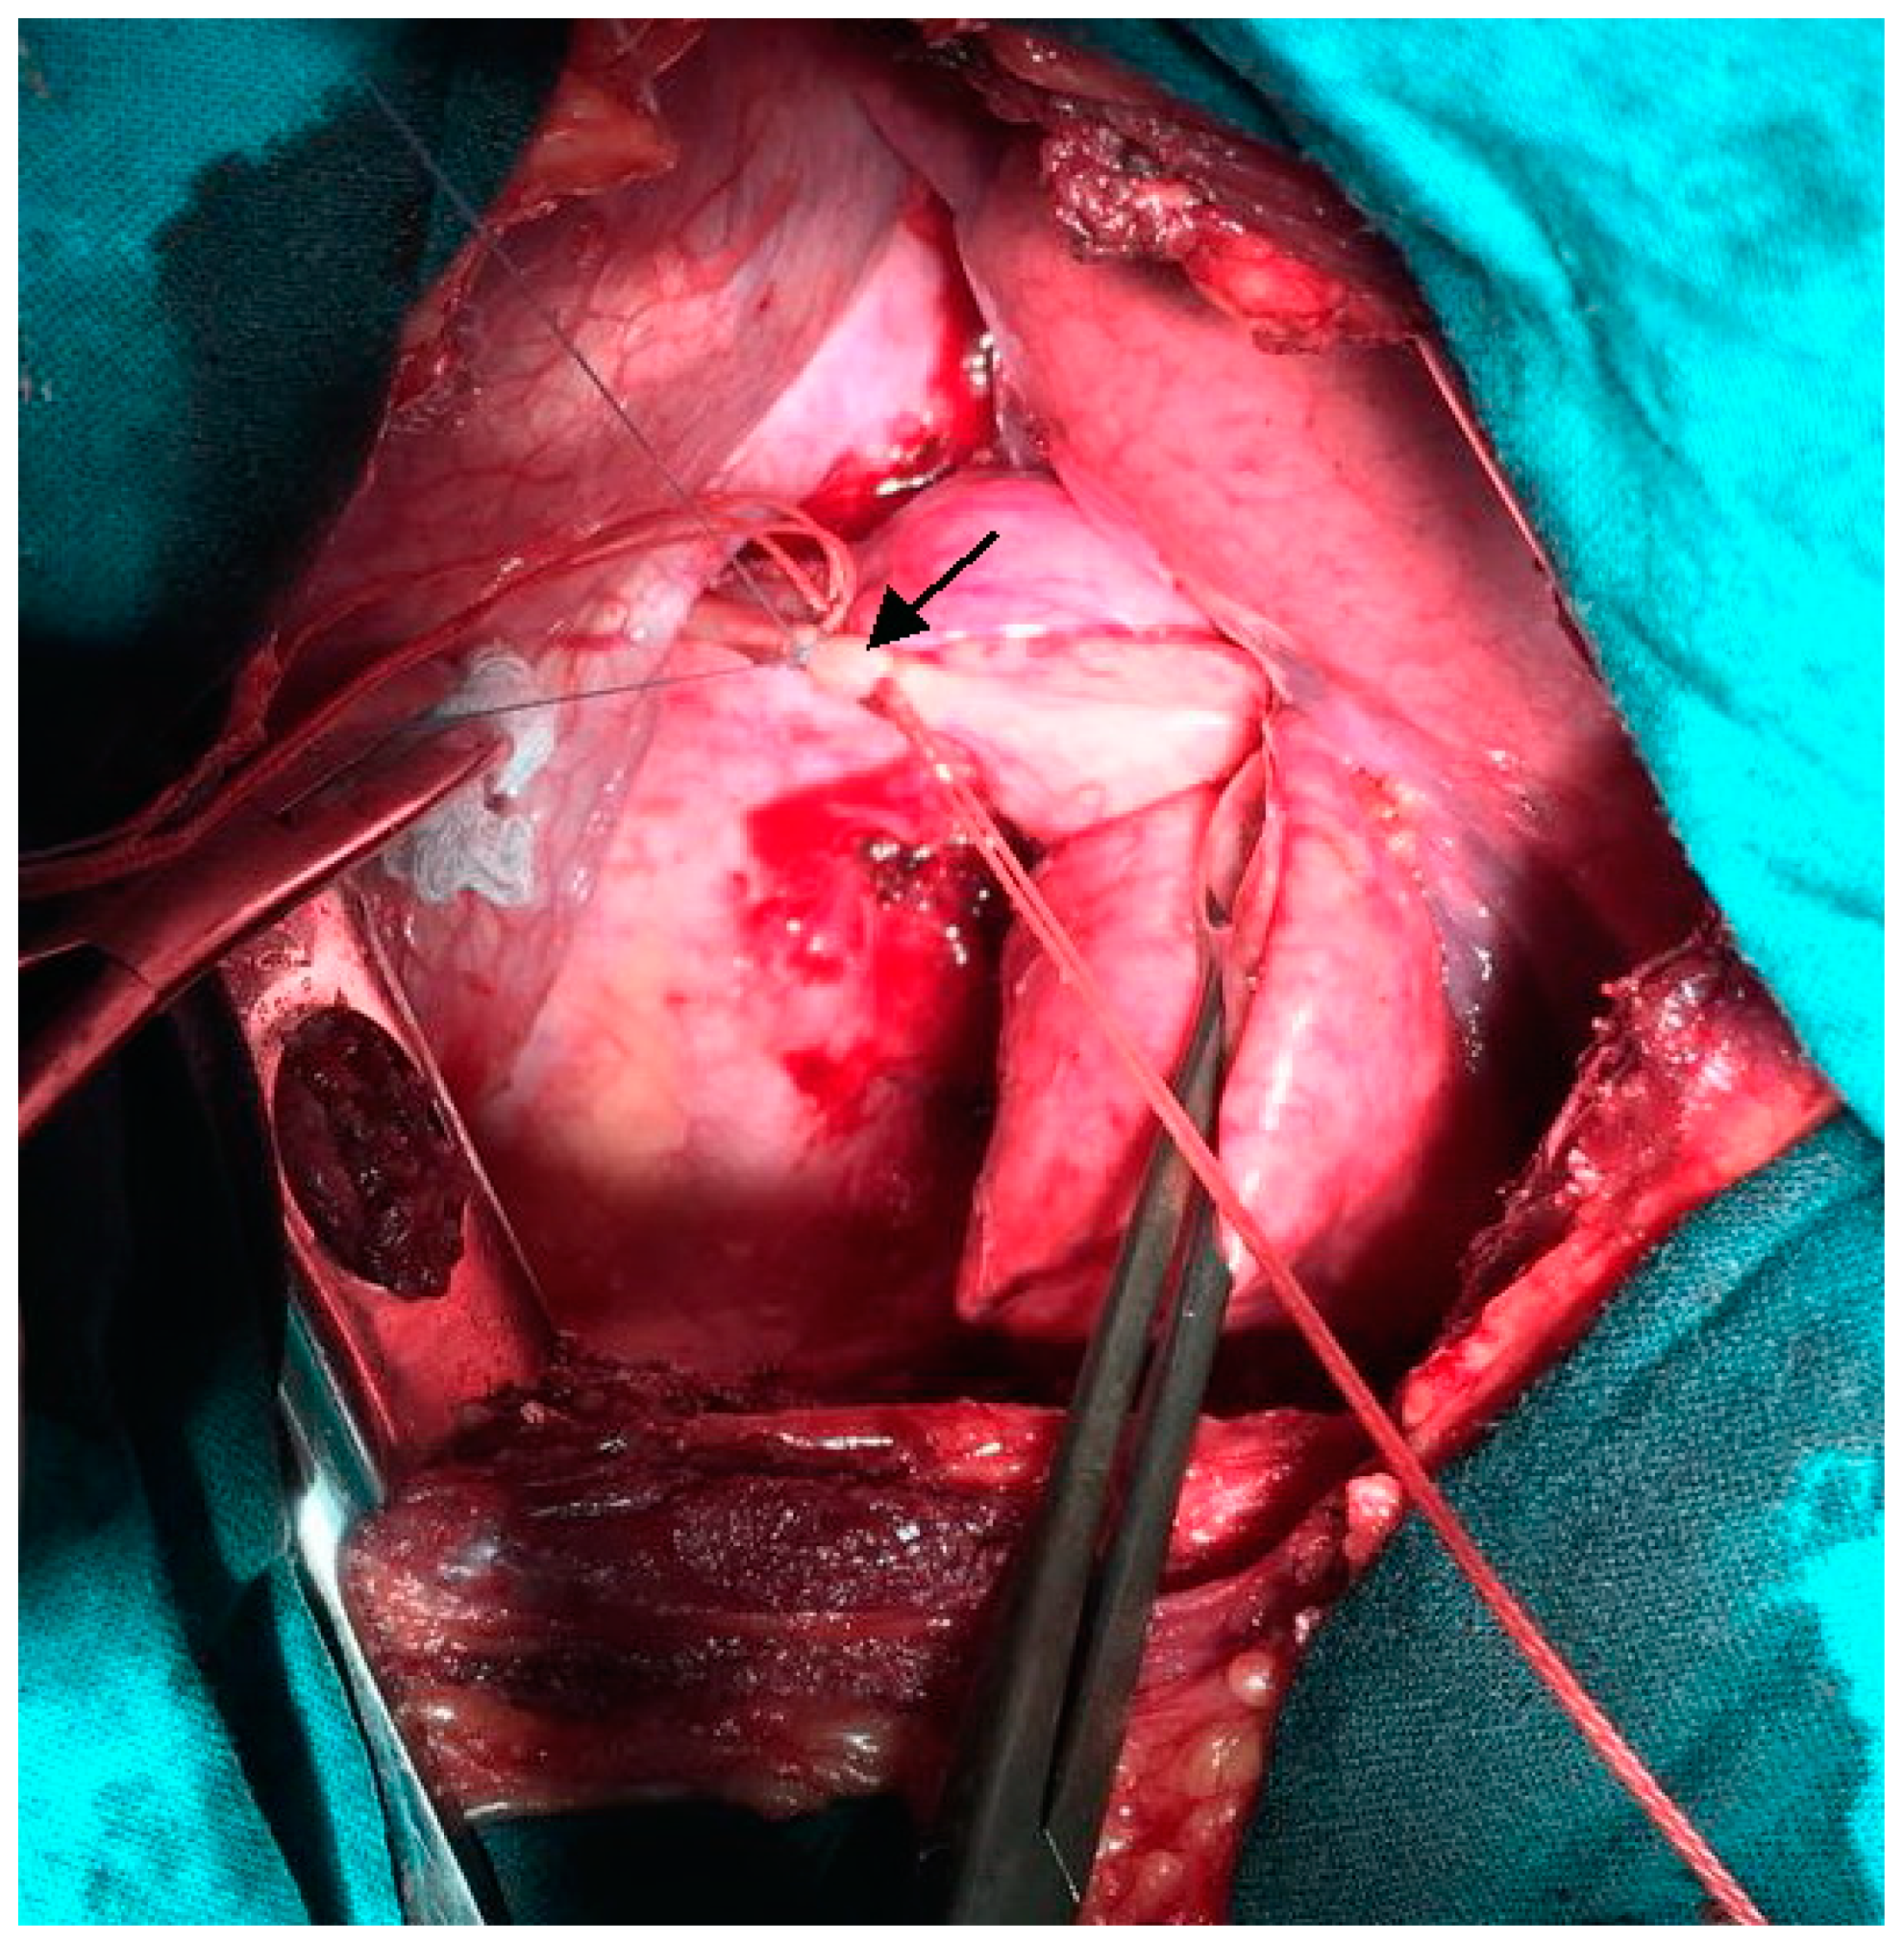

We performed left-sided posterolateral thoracotomy in the seventh intercostal space. The intrapulmonary sequester was characterized by an unventilated area of lung tissue at the posterior-basal segment (S10) of the inferior lobe. In accordance with CT findings, the pulmonary sequester was supplied by an arterial vessel with a diameter of 5 mm. The artery traversed the diaphragm. We ligated the artery carefully before transection (Figure 3).

The postoperative course was without complications. Plain X-ray studies of the thorax obtained before the girl was discharged from the hospital confirmed the absence of infiltrates and pneumothorax (Figure 4).

Figure 3. Intra-operative photograph: Ligation of the anomalous feeding artery (indicated by arrow) supplying the pulmonary sequester.

Figure 4. Plain X-ray image of the thorax obtained before discharge from hospital: normal appearance of left lung after resection of the pulmonary sequester.